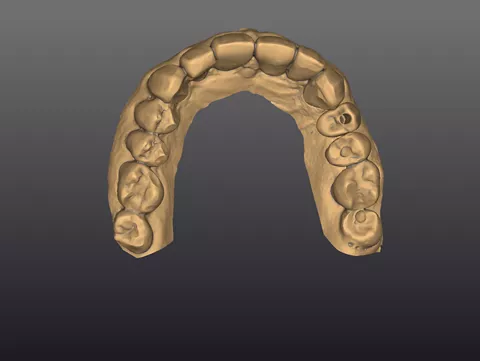

2a. 2b. Preoperative frontal and occlusal view of the lower arch showing multiple missing teeth.

2b

3a. 3b. Implant and Healfit® SH planning in coDiagnostiX®.Digital smile design illustrating esthetic outcome using Smilecloud®.

3a

3b